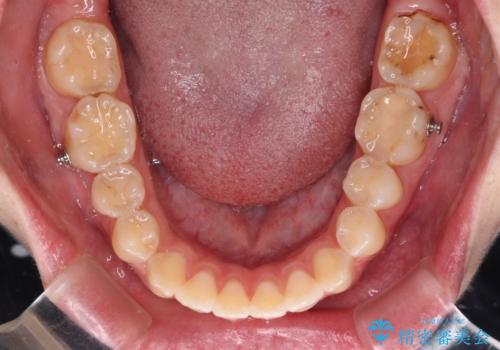

開咬を治す インビザラインによる矯正治療

- 上下前歯の開咬を気にして来院された患者様です。

開咬はインビザラインを用いると有意に改善ができるため、インビザラインによる矯正治療を行うこととしました。

途中1年8ヶ月ほど来院されず、久しぶりの来院後は治療が面倒とのことで、前歯の叢生や隙間に不十分な点が残った状態での終了となりました。